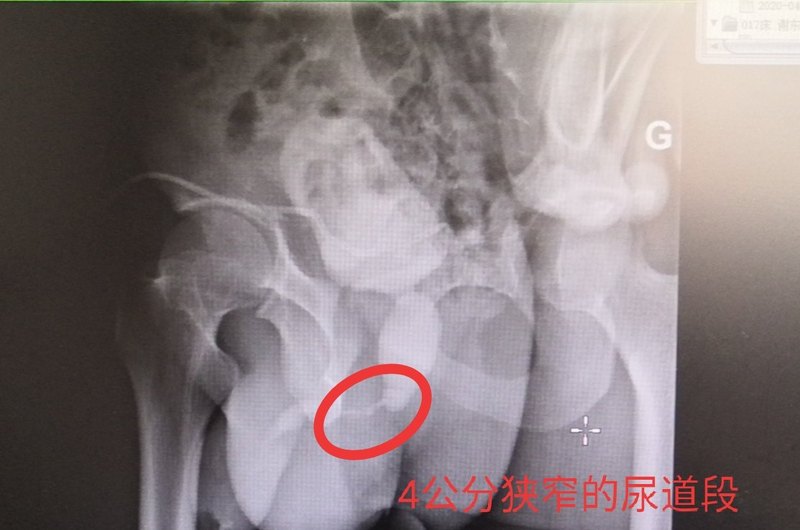

尿道损伤-经典病例系列1:骨盆骨折合并尿道断裂一、患者基本情况:1、患者男性,32岁。2021年5月因车祸伤致骨盆骨折、尿道断裂。2、外院急诊予以留置膀胱造瘘管,定期更换造瘘管。伤后半年外院行尿道吻合术,术后4周拔出导尿管后出现排尿困难。二、我院治疗方案:1、检查:半年后转诊至我院,完善尿道造影、尿道镜检查示球膜部尿道闭锁,长度约3cm。2、手术:当月我院行尿道吻合术,术中切除尿道瘢痕及局部组织瘢痕后发现尿道吻合困难,缺损长度约5cm,遂行耻骨下缘切除+尿道吻合术。三.术后恢复情况:术后4周拔出导尿管后自主排尿通畅,一周后拔出膀胱造瘘管。上海市第六人民医院泌尿外科撒应龙医生的门诊时间周三上午,专家门诊,上海市徐汇区宜山路600号(总院)门诊十楼B区周二上午,周三下午,特需门诊,上海市徐汇区宜山路600号(总院)门诊十三楼

曾铭强 湖南省人民医院泌尿外科主治医师 膀胱尿道造影x线检查发现后尿道闭锁的部位和长度。 三维ct成像显示膀胱尿道的立体结构、与直肠的关系,以及骨盆的稳定性和恢复情况。 车祸、工伤容易导致重要脏器破裂出血、全身多处骨折,如果发生严重的骨盆骨折,还容易并发男性尿道断裂、尿道出血,导致后尿道狭窄或闭锁。发生尿道狭窄的病人,常常出现尿频、尿急、排尿困难等症状,长期梗阻可导致肾功能衰竭等;如果发生尿道闭锁,尿液无法排出,往往需要先行尿流改道、留置膀胱造瘘管,待病情稳定后再接受尿道复通手术。 55岁的黄先生是湖南娄底人,5个月前在工地上被小型挖掘机碾压下腹部,导致骨盆多处骨折、左股骨骨折、失血性休克。在当地医院接受了急诊骨盆骨折固定手术、大量输血等。经过5个月的康复治疗后,患者为求尿道复通手术经当地医生介绍,找到湖南省人民医院泌尿二科曾铭强博士,以“创伤性后尿道闭锁”收住院。 入院后,经过膀胱尿道造影X线检查发现后尿道闭锁的部位和长度,了解了患者尿道损伤部位没有假道、瘘管发生;骨盆和膀胱尿道三维CT成像显示膀胱尿道的立体结构、与直肠的关系,以及骨盆的稳定性和骨折的恢复情况。 术前诊断中,利用膀胱软镜分别从尿道外口进入观察断端远段尿道、从膀胱造瘘口进入观察断端近段尿道的情况,发现前列腺尖部有一片状的结石,也没有发现尿道损伤部位有假道和瘘管形成。通过充分的术前准备后,曾铭强医师等为患者成功实施 “后尿道闭锁段切除+端端吻合术”。术中通过充分暴露、彻底清除瘢痕组织、止血等措施后,行远、近端尿道无张力吻合。 患者术后恢复好,48小时后即可下床适量活动,术后1周出院。